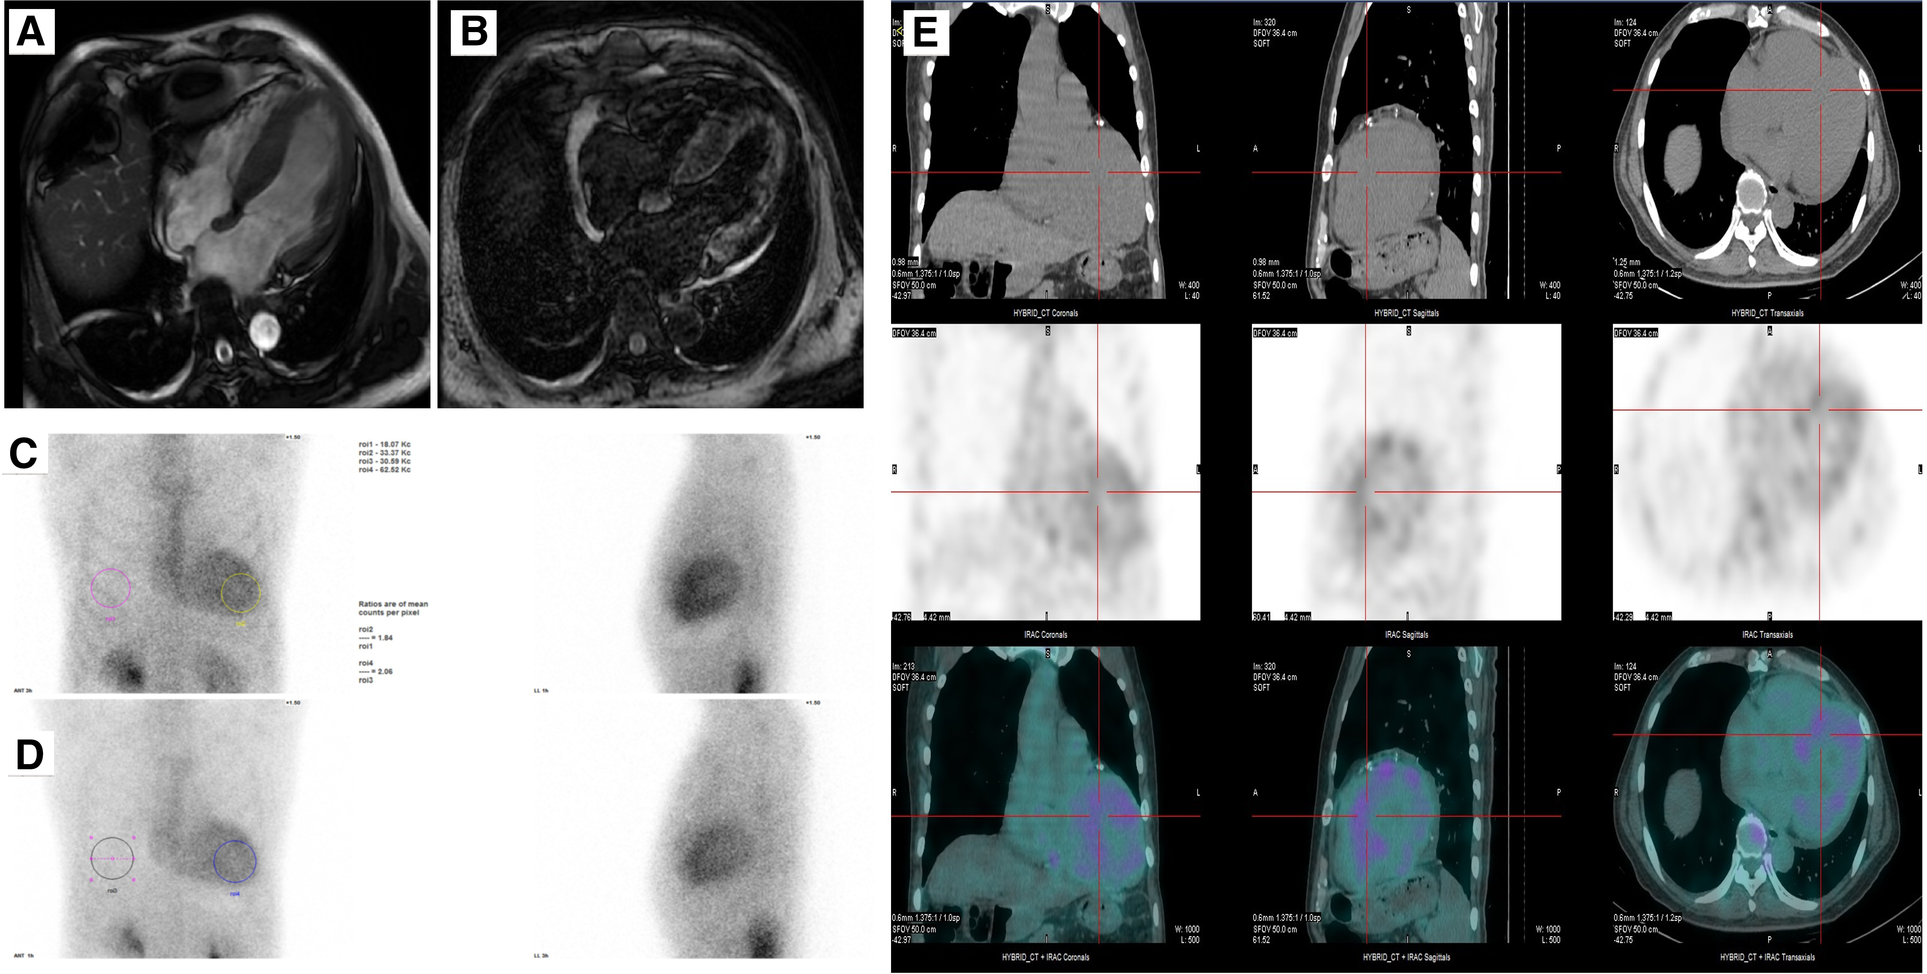

Cardiac magnetic resonance was then used to evaluate cardiomyopathy due to his diffuse hypertrophy and reduced EF value. The first-pass perfusion imaging showed decreased subendocardial perfusion in the left ventricular walls. Delayed-enhancement magnetic resonance imaging revealed the left ventricle with diffuse granular enhancement, mainly under the endocardium (Figures 2A,B). The patient had no family history of amyloidosis. Serum kappa, lambda light chains, and kappa/lambda free light chains ratio were normal, and no monoclonal protein was detected. Subsequently, a SPECT imaging using 99mTc-PYP scintigraphy was done. The result showed a significantly higher cardiac uptake than bone (SQA grade 3), indicating the possibility of transthyretin amyloid deposition (Figure 2C–E). A genetic analysis of the TTR was then performed, and the result revealed a rare mutation NM_000371.4 c.172G>T resulting in p.D58Y for the Chinese population (chr18:31592998-31592998, human genome 38).

Figure 2

(A,B) Cine and late gadolinium-enhanced MRI. (C–E) A SPECT imaging using 99mTc-PYP scintigraphy showing uptake of 99mTc-PYP by cardiac at 3 h and 1 h.